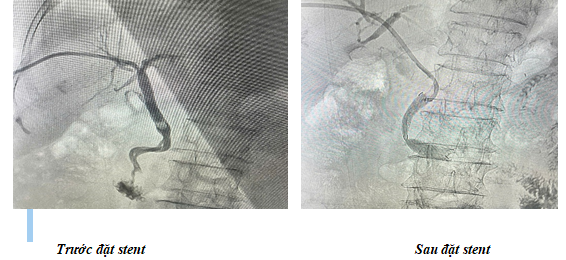

PTC được áp dụng khi ERCP không thực hiện được. Bác sĩ chọc kim qua da vào gan, bơm chất cản quang và quan sát đường mật trên X-quang. Sau khi xác định vị trí tắc, dây dẫn và stent sẽ được đưa vào để mở rộng đoạn hẹp. PTC thường được chỉ định cho các trường hợp tổn thương khó tiếp cận qua đường nội soi.

Sau khi ống thông dùng trong chụp mạch đi qua vị trí tắc nghẽn, thông xuống tá tràng, bác sĩ thay dây dẫn ái nước bằng dây dẫn cứng Amplatz, thay đường vào can thiệp phù hợp với yêu cầu của stent (cụ thể, với stent che phủ có đường kính 10mm thì đường vào can thiệp có thể phải là loại 10F). Stent sẽ được đưa qua da bệnh nhân, theo dây dẫn cứng Amplatz đi qua vùng hẹp. Chiều dài của stent phải lớn hơn vị trí hẹp ống mệt nhưng không nên dài quá vì có thể gây tắc các nhánh mật bên. Trong trường hợp sử dụng stent che phủ, cần lựa chọn kích thước phù hợp với tổn thương;